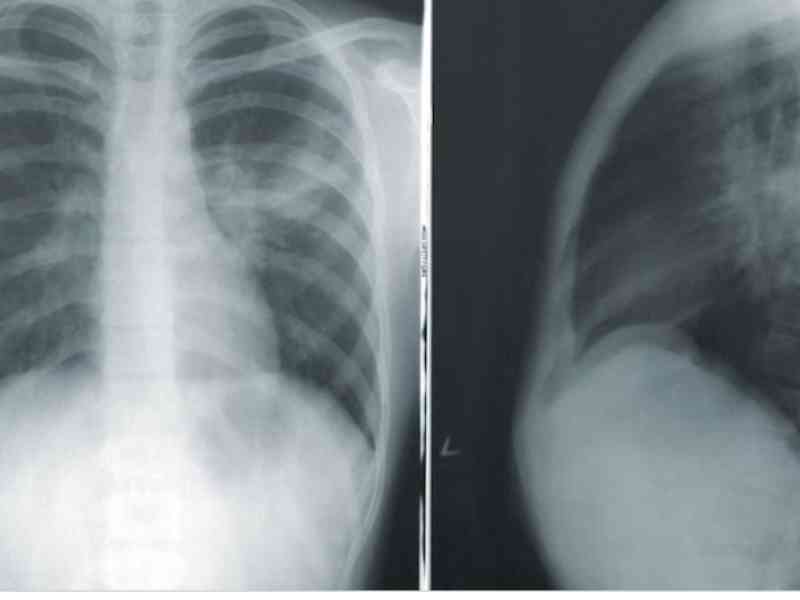

50. Not A Typical X-ray Image